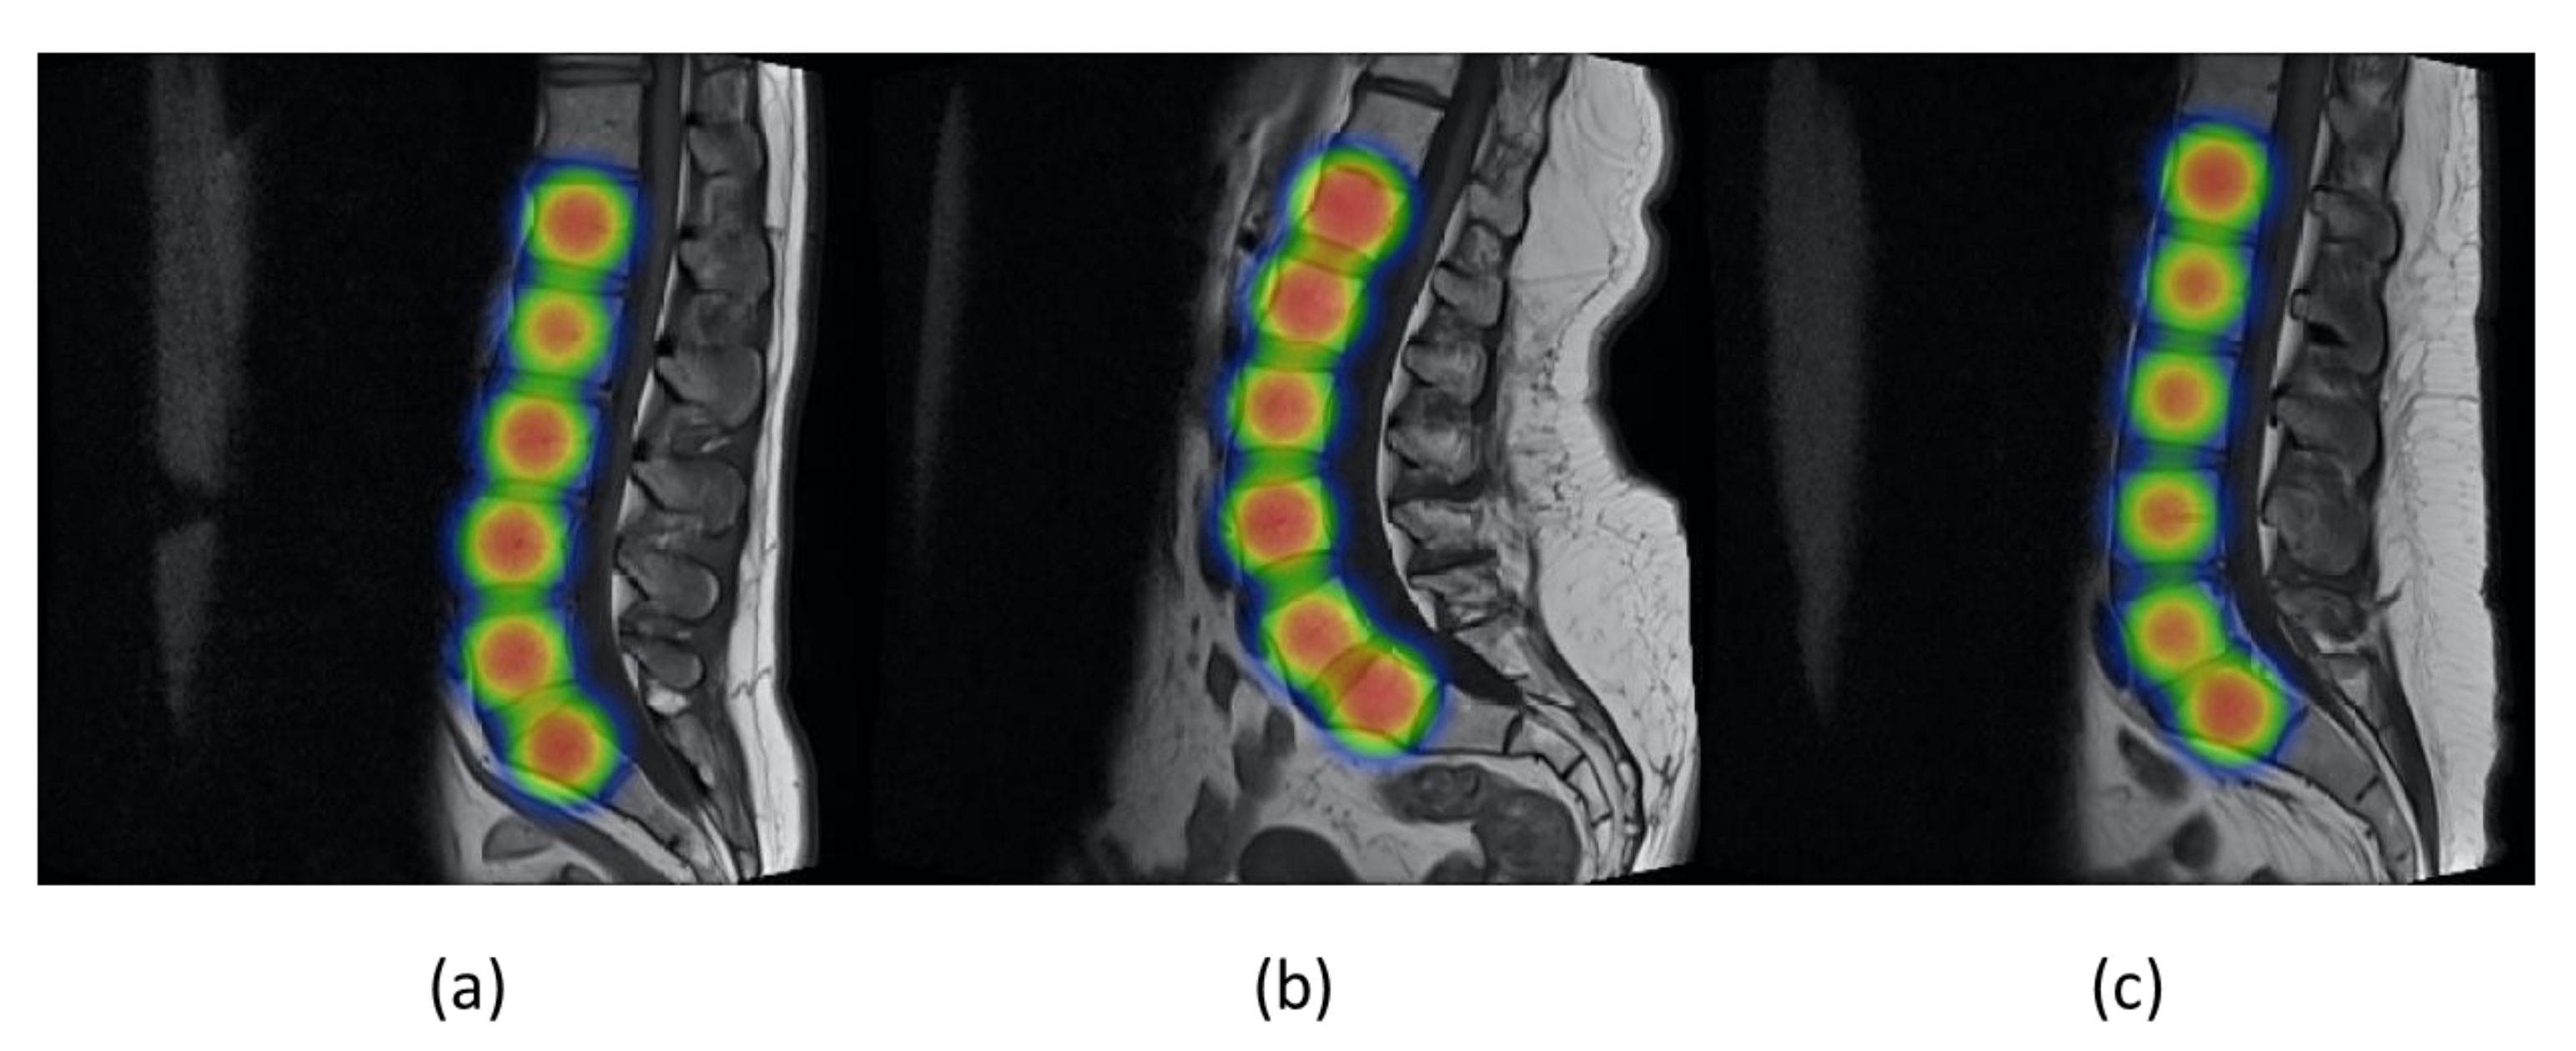

Figure 11 shows the values of precision and recall of object detector YOLOv5 with increasing values of epoch from 0 to 90. Mean average precision (mAP) is the mean of average precision, and we obtained mAP of 0.975 by using YOLOv5s. YOLOv5 can be visualized in heat maps from its trained weights before applying non-maximum suppression, as shown in Figure 12.

Figure 12. (ac) represent the YOLOv5 visualization in heat maps obtained from its weights after training on the three different images.